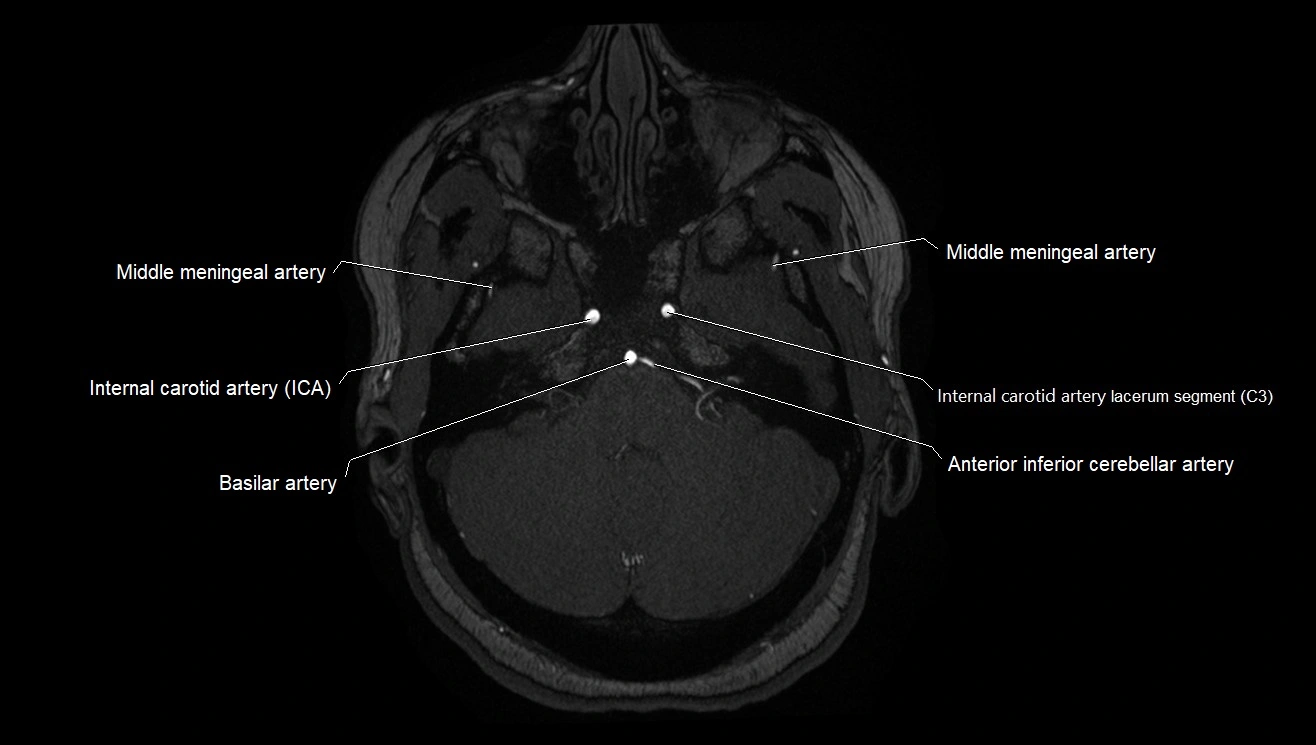

MRI images

image